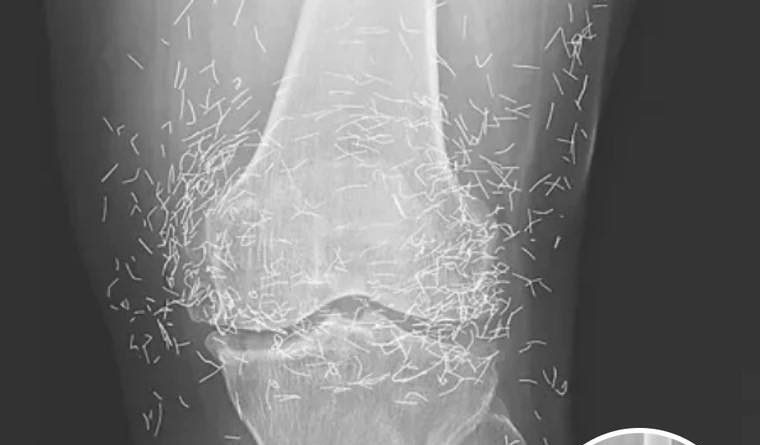

Doctors Stunned After Looking At This X-Ray Of Woman Suffering Joint Pain

A routine X-ray revealed an unexpected surprise when doctors examined the knees of a 65-year-old woman suffering from severe joint pain. What they found was nothing short of astonishing — hundreds of tiny gold needles embedded deep in her tissue.

A X-ray of the patient’s knee showing acupuncture needles embedded in the tissue, Photo Credit: Reddit

As for the South Korean woman, her case was recently documented in the New England Journal of Medicine. While the needles may have been intended to help, her X-rays tell a cautionary tale about the potential risks of extreme alternative therapies.